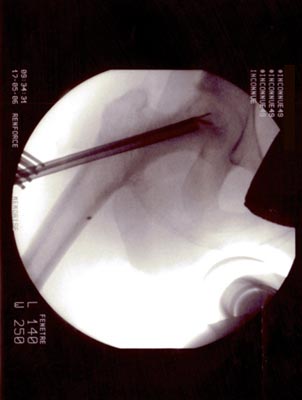

Technique opératoire Le trocart est introduit par voie pertrochantérienne et suit le trajet de la vis. Sa position dans la tête fémorale et dans la nécrose est repérée sous amplificateur de brillance de face et de profil. Une petite pince à séquestre retire les tissus fibreux et nécrosés circonférenciellement après repérage. Un lavage au sérum bétadiné complète le curetage. La moelle osseuse est prélevée (à l'aide du trocart de Mallarmé) sur la crète iliaque selon la technique classique. La moelle recueillie est d'autant plus riche en cellules souches qu'elle a été aspirée par petites fractions (2 ml). Ceci permet de réduire le degré de dilution par le sang périphérique. Elle est ensuite mélangée extemporanément avec le biomatériau. En général : 5 ml pour 5 cc de corail naturel. Sous contrôle Rx., le greffon est introduit à l'aide d'un trocart jusque dans la tête au niveau de la zone curetée : L'appui-contact avec 2 C.B est immédiat. Faut-il mettre en décharge avec traction et combien de temps ? Il ne sera possible de répondre à cette question que lorsque l'on saura avec précision la durée des phases de déminéralisation-reminéralisation du composite biomatériau-moelle osseuse aboutissant à de l'os néo- formé mécaniquement solide. C'est aux fondamentalistes de nous apporter la réponse.

OSTEONECROSE ASEPTIQUE de la H.D. Intervention en mai 2006